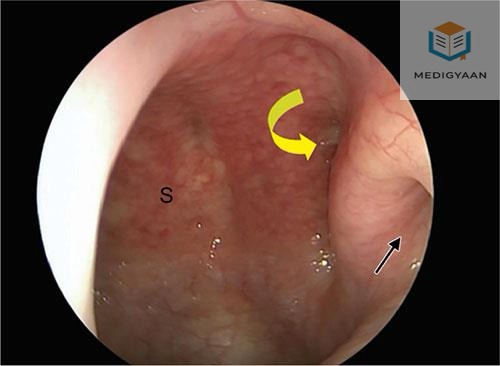

Question Image